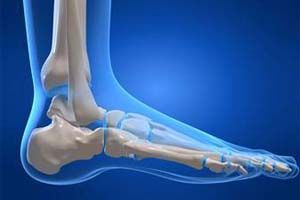

Лодыжка — это отросток кости, который помогает образованию голеностопного сустава. Часто травмирование лодыжки происходит после неожиданного падения на ногу или на тренировочном процессе.

Перелом лодыжки — нарушение целостности сустава, провоцировать которое может усиленный поворот стопы внутрь, опущение свода стопы, отведение ее или к центральной оси тела, или от нее.

Голеностоп состоит из латеральной и медиальной лодыжек. Их повреждение — чаще результат сильного удара, приходящегося на прямые ноги при прыжке, беге, упавшей тяжести на стопу, неудачного подворачивания ноги при беге или ходьбе.